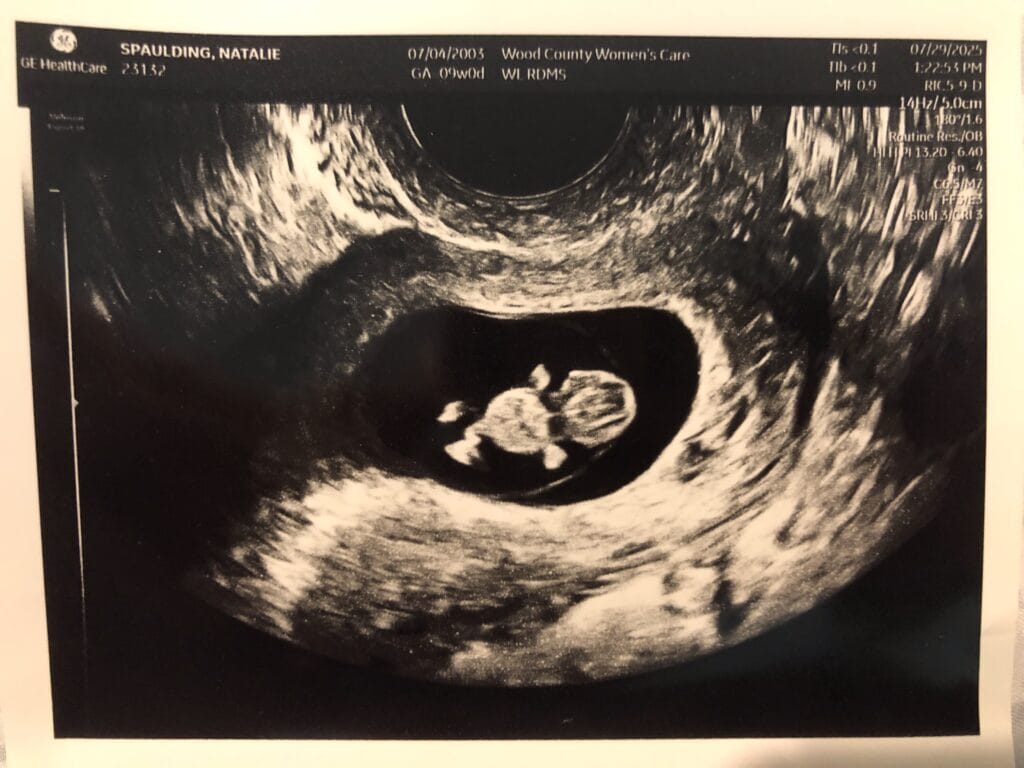

A Real Human Life: My Baby at 9 Weeks

State of Alaska Appeals to the Supreme Court, Challenging 2024 Planned Parenthood-backed Ruling

By Natalie Spaulding

On October 29, 2025, Attorney Laura Wolff argued in front of the Alaska Supreme Court against the Court’s 2024 decision to continue suspension of a 1970 law requiring abortions to be performed only by licensed physicians.